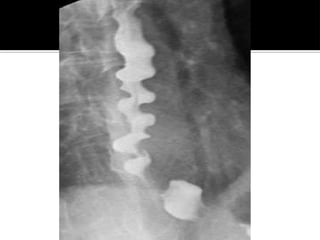

Strong, non-peristaltic contractions of the

esophageal body

Often precipitated by by ingestion of hot

and cold liquids

 Patients have normal sphincter function

 Associated with GERD

•Upper GI/esophageal contrast study

• shows "corkscrew esophagus"

•Manometry

• may show high-amplitude,

simultaneous contractions (non-

peristaltic)